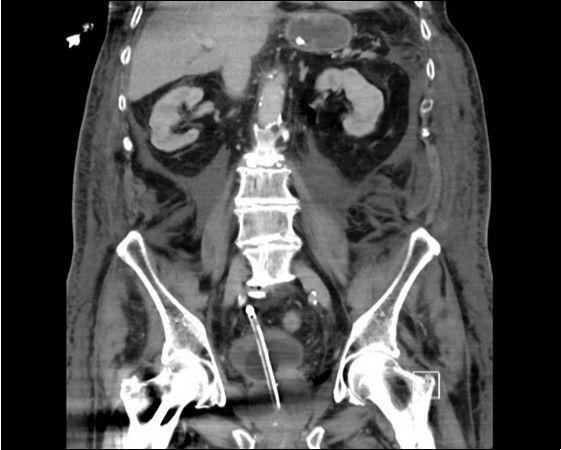

An urgent CT abdomen revealed a bladder perforation with the tip of the irrigating catheter situated in the abdominal cavity (Figure 1, Figure 2, Figure 3a,Figure 3b). This was most likely due to over-insertion of the 3-way catheter due to the extra force required because of the benign prostatic hypertrophy. He had therefore been receiving normal saline as ‘peritoneal dialysis’ with normal saline since insertion of the catheter. The catheter was withdrawn, and the patient made a full recovery.

Figure 3b.horizontal plane CT image

horizontal plane CT image